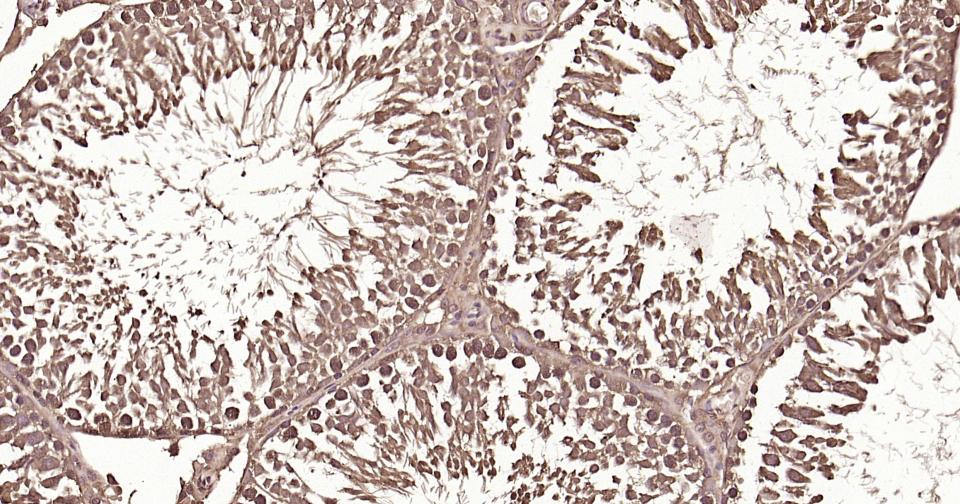

Paraformaldehyde-fixed, paraffin embedded Human Testicles; Antigen retrieval by boiling in sodium citrate buffer (pH6.0) for 15 min; Antibody incubation with Ubiquitin Monoclonal Antibody, Unconjugated(bsm-63008R) at 1:200 overnight at 4°C, followed by conjugation to the bs-0295G-HRP and DAB (C-0010) staining and DAB (C-0010) staining.